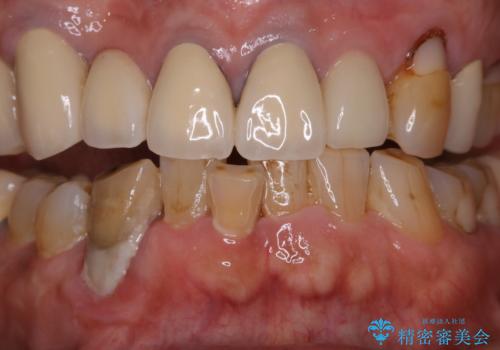

半年ぶりのクリーニング PMTC

- 半年、来院できなかったためきれいにクリーニングしたいとのことでした。久しぶりだったことと、全体的に汚れが付着していたためPMTC60分コースを行いました。